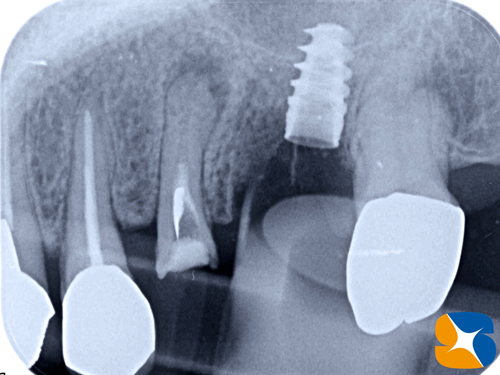

抜いた跡のところを一部削って、インプラントを移植しました。

※ノーベルバイオケア社製:アクティブ直径4.3㎜ × 深さ8.5㎜

約2時間ほどの施術が無事に終了しました。

本日の治療内容は

・抜歯

・徹底した膿の排出

・ソケットリフト(骨の厚みを6㎜→10㎜にボリュームアップ)

・インプラントの移植

・骨の再生療法

・超早期の歯肉回復でした。